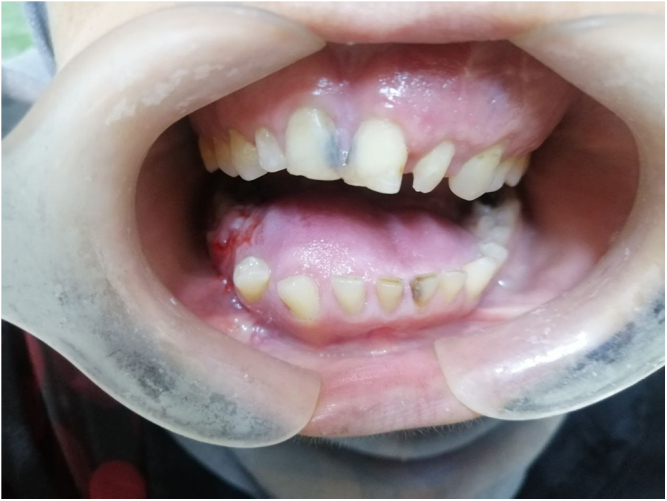

Case presentation: A 24-year-old female with chronic kidney disease (CKD) and hypertension presented with progressive teeth displacement, mobility, and facial asymmetry. Radiographic evaluation revealed a well-defined radiolucent lesion affecting both jaws, displacing teeth, and perforating the cortical bone. Biopsy confirmed the diagnosis of TrJOF. Due to the aggressive growth and contraindications for chemotherapy or radiation therapy, surgical excision was performed. Postoperatively, the patient remains under observation, with ongoing management of CKD to prevent complications and ensure recovery.